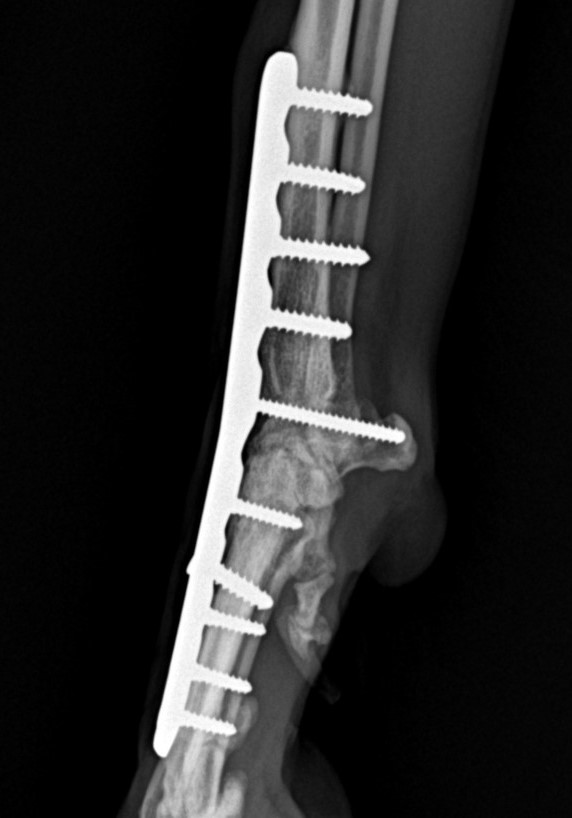

Artrodéza karpálního kloubu

Případy z praxe

Akutní

případ